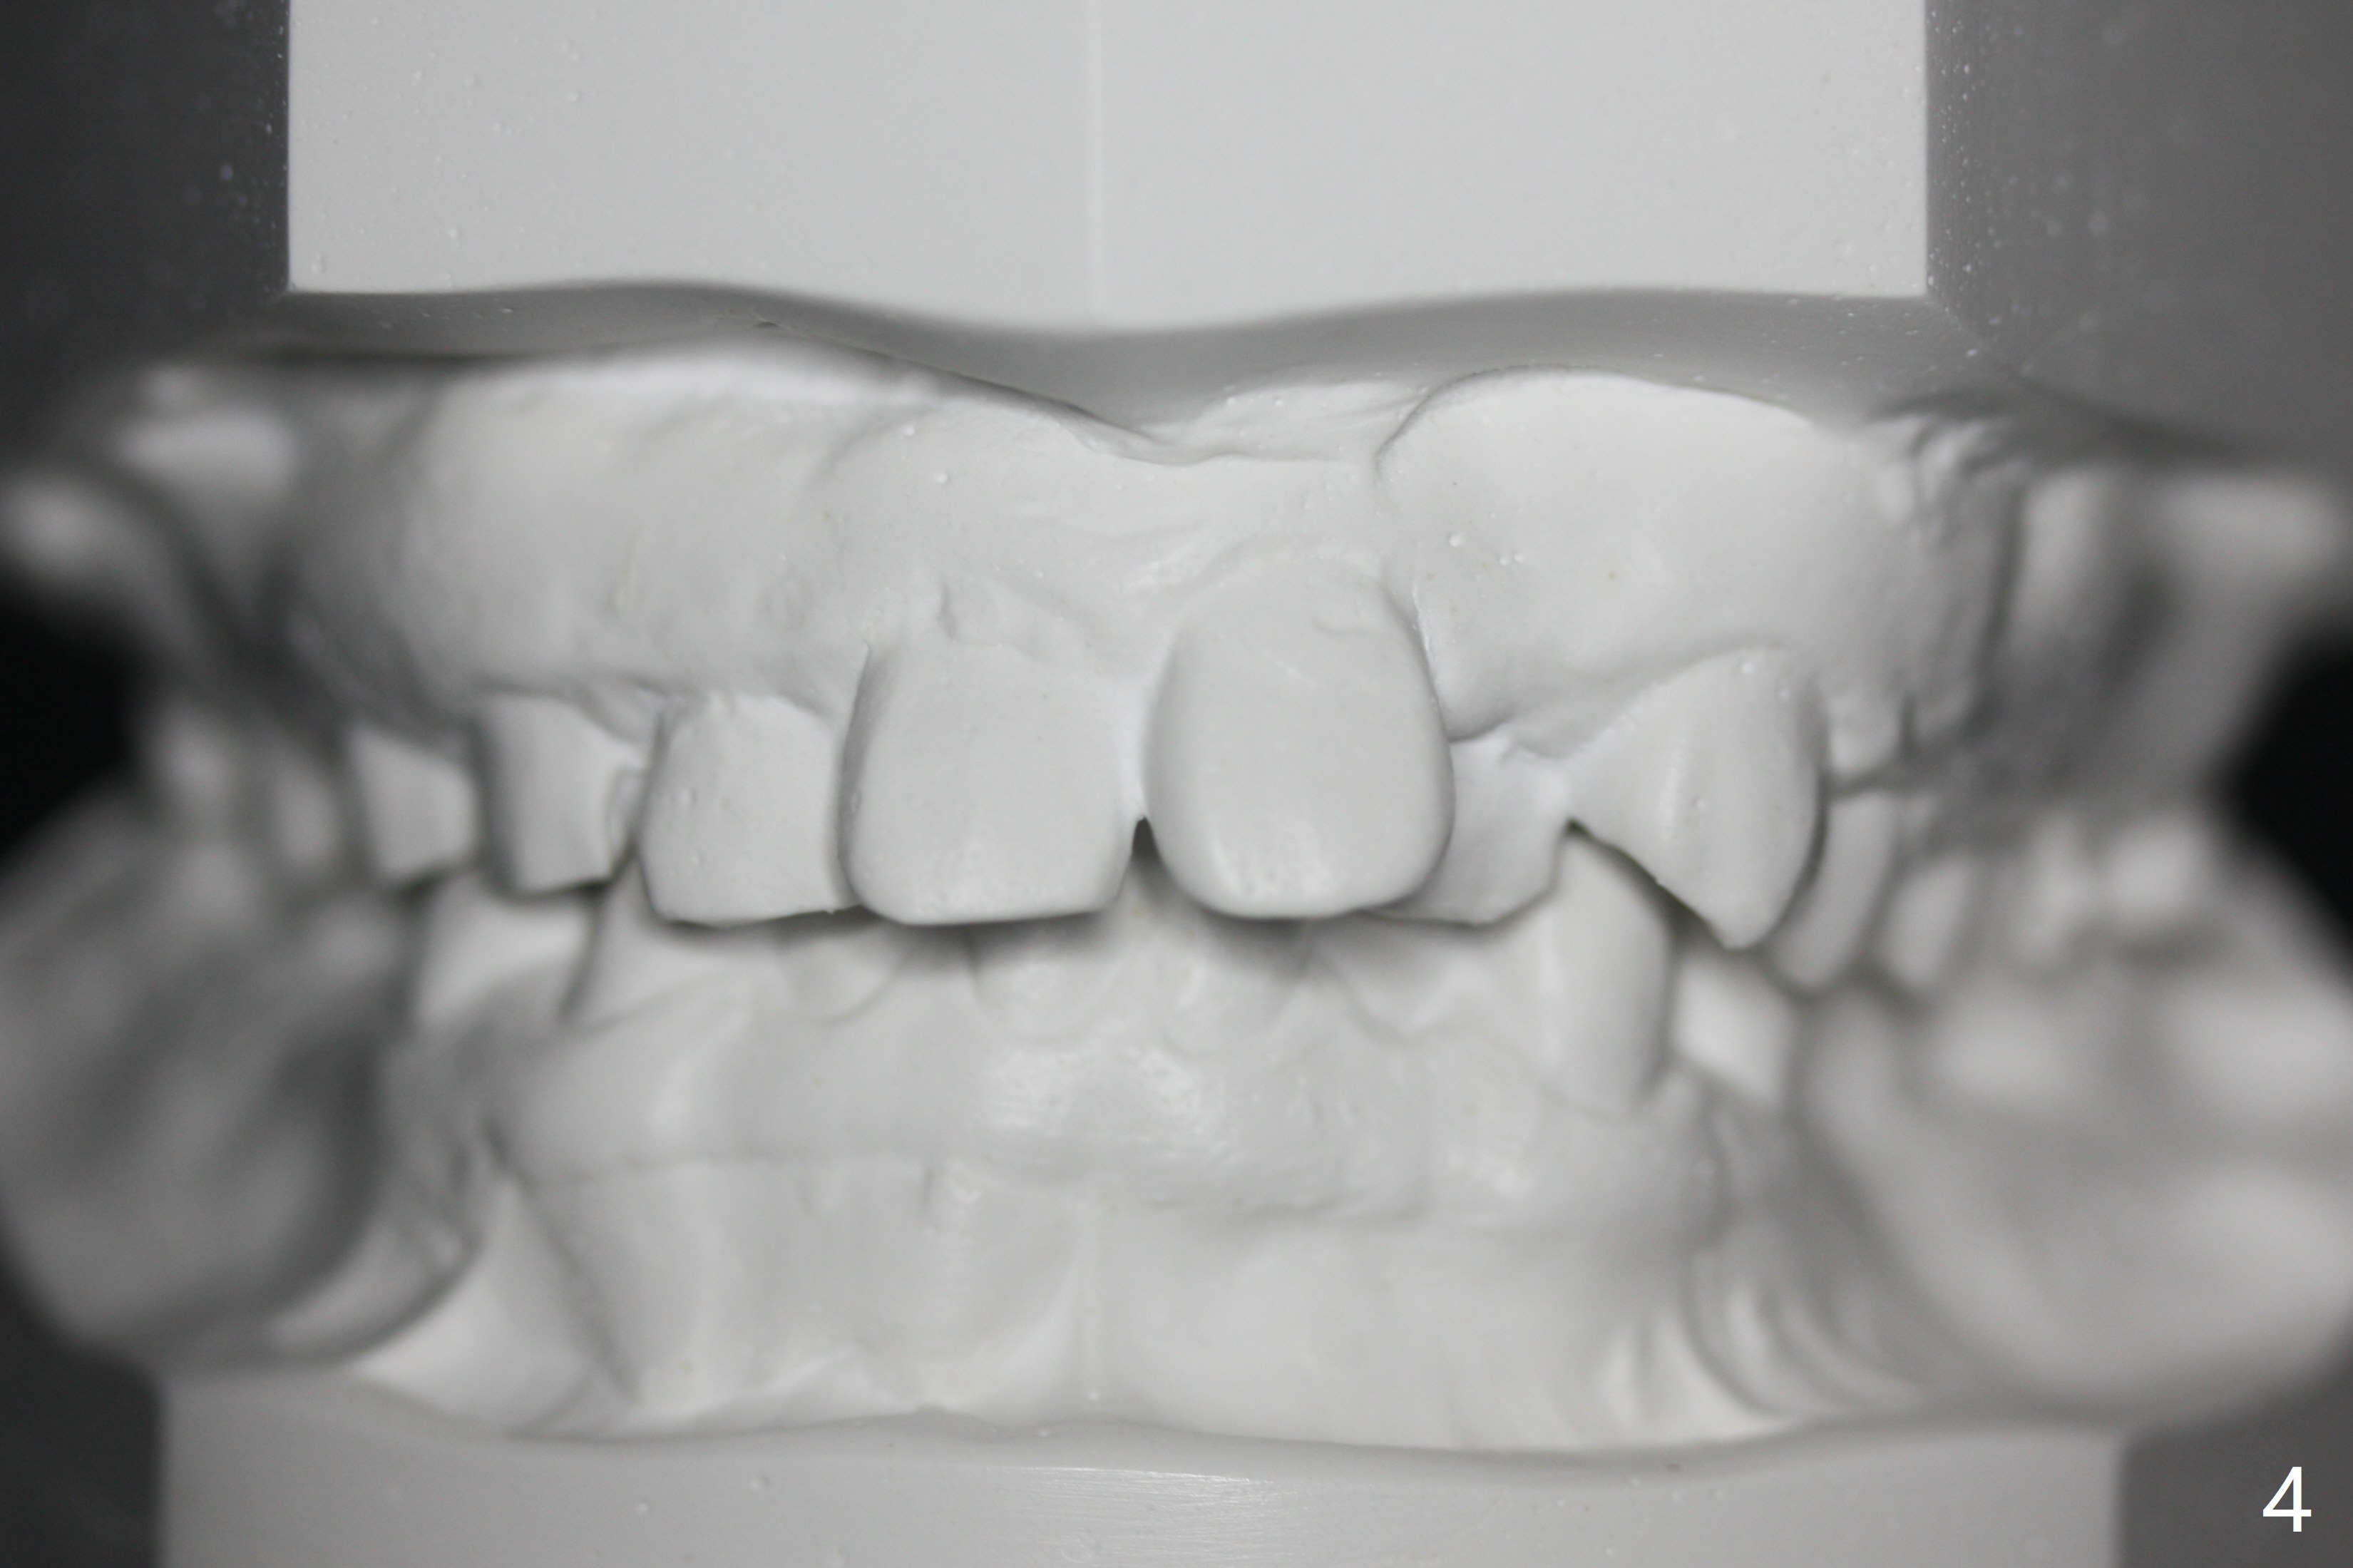

A 32-year-old man has had severe crowding for the last 10 years (Fig.1-5).  He is ready for orthodontic treatment now.  LL5 has been extracted for 4 years (Fig.1 x).  Severe caries at UR5 makes it easy to decide for extraction (Fig.2 x), while it is hard to determine which of the LR bicuspids needs to be extracted because of moderate caries at LR5 and even harder for UL because of caries at UL6,7 (Fig.2 *).

In fact impression for models (Fig.3-7) is taken after UL caries control.  Sedative filling is done at UL1,3 (Fig.6 *) and definitive restoration will be done when crowding resolves.  The defects at UL6,7 (Fig.6 x) is so extensive that after composite molar bands are placed immediately for retention.  Amazingly, there is no symptom after UL6,7 restoration.  Therefore UL4 will be extracted for crowding resolution.  UR 5 (Fig.1-3,6) has been extracted, while LR5 (Fig.2,7) will be.